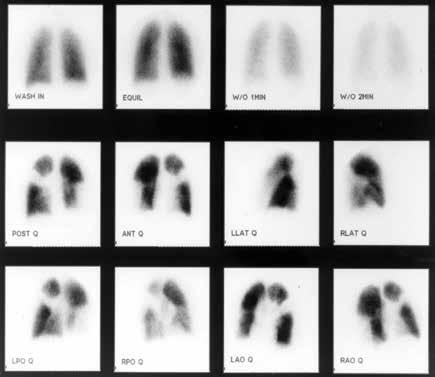

Chronic Thromboembolic Pulmonary Hypertension

There are several categories of pulmonary hypertension. WHO Group I includes patients with idiopathic pulmonary hypertension, familial pulmonary hypertension, drug and toxin related (fen-phen) portopulmonary hypertension, HIV related pulmonary hypertension and pulmonary arterial hypertension associated with connective tissue disorders (such as scleroderma). WHO Group II pulmonary hypertension is often referred to as pulmonary venous hypertension. This includes patients with left ventricular systolic or diastolic dysfunction or valvular heart disease. Essentially, the WHO Group II category includes patients who have an elevated pulmonary capillary wedge pressure and/ or elevated left ventricular end diastolic pressure. WHO Group III pulmonary hypertension consists of patients with COPD, interstitial lung disease, or other conditions in which hypoxia causes vasoconstriction. The remainder of this article will focus on WHO Group IV pulmonary hypertension (chronic thromboembolic pulmonary hypertension or CTEPH). Although WHO Group IV patients are relatively rare, it is crucial to identify them because this is the only type of pulmonary hypertension which is potentially surgically curable.

After acute pulmonary embolism, most patients will recover and have normal pulmonary hemodynamics, gas exchange, and exercise tolerance. It is believed that 1-4% of patients with acute pulmonary embolism will go on to develop CTEPH within two years. It is not clear why some patients with acute pulmonary embolism develop CTEPH. Risk factors include hypercoagulable states, myeloproliferative syndromes, splenectomy and chronic indwelling central venous catheters. Patients with CTEPH present with dyspnea, which can have a gradual onset. Many patients with CTEPH will not have a known previous diagnosis of acute pulmonary embolism. As with other patients with pulmonary hypertension, patients with CTEPH may not show findings on physical exam until pulmonary hypertension is in the late stages. Findings include a right ventricular lift, jugular venous distention, fixed splitting of the second heart sound, hepatomegaly, ascites, and peripheral edema. Patients with CTEPH may have “flow murmurs” heard over the lung fields because of turbulent flow through partially obstructed or recanalized pulmonary arteries. These tend to be accentuated during inspiration.

Acute pulmonary embolism is the trigger for CTEPH. In some patients this triggers a small vessel vasculopathy (for unclear reasons) that contributes to the extent of pulmonary hypertension. This may explain why up to 35 percent of patients who undergo succesful pulmonary thromoendarterectomy can have some degree of postoperative pulmonary hypertension.

Although VQ scanning has become less commonly used for diagnosis of acute pulmonary embolism this remains the initial imaging study of choice in patients with pulmonary hypertension

to separate “small vessel” variants (Idiopathic pulmonary arterial hypertension) from “large vessel” disease (CTEPH) A normal VQ scan essentially excludes the diagnosis of CTEPH. A scan with one or more mismatched segmental defects is suggestive of the diagnosis. However, it is important to note that VQ scan can often understate the extent of central pulmonary vascular obstruction. Once the VQ scan is found to be abnormal then further testing should be undertaken (such as CT angiogram and/or pulmonary angiography). The angiographic findings in CTEPH are distinct from those of acute pulmonary embolism. They can include pouch defects and pulmonary artery webs. Patients with severe pulmonary hypertension have been found to tolerate performance of angiography as well as VQ scan without significant complication rate.

The surgery for CTEPH is quite different from surgical intervention for an acute pulmonary embolism. Surgery for CTEPH is called a pulmonary thromboendarterectomy (PTE), which requires median sternotomy and cardiopulmonary bypass. It requires an often tedious intimal dissection of fibrotic recannalized thrombus from the native pulmonary arterial wall. IVC filter placement is usually recommended before pulmonary thromboendarterectomy. These patients can have a complicated postoperative course and this type of surgery is only done at a few specialized centers in the country. The center which is best known for this type of surgery is the University of California (San Diego). Patients who have undergone PTE are typically maintained on lifelong anticoagulation. To be a candidate for this surgery, a patients must have central, surgically accesible chronic thromboemboli. A significant postoperative complication is pulmonary artery steal, which refers to redistribution of pulmonary arterial blood flow from well-perfused segments into the newly opened segments resulting in ventilation perfusion mismatch and hypoxia. This redistribution of flow resolves over time. Approximately, 30% of PTE patients can develop reperfusion pulmonary edema. The perioperative mortality of pulmonary thromboendarterectomy can be in the range of 2-3% in experienced centers. Outcome is clearly better in high voluime centers (more than fifty PTE surgeries/year). Approximately 5000 thromboendarterectomy procedures have been performed worldwide, 3000 at UCSD alone.

Surgery for CTEPH is clearly the best therapeutic option. However, there are some patients with CTEPH who are inoperable or who have persistent or recurrent pulmonary hypertension after undergoing pulmonary thromboendarterectomy. There is now a medical therapy available for these patients. Riociguat (Adempas) was approved by the FDA in October 2013. It is a member of a new class of compounds-soluble guanylate cyclase stimulators. In the multicenter study by Ghofrani et al that was published in the New England Journal of Medicine in July 2013,

FLORIDA MD - SEPTEMBER/OCTOBER 2023 8 PULMONARY AND SLEEP DISORDERS

261 patients were randomized prospectively to receive riociguat versus placebo. Riociguat was shown to significantly improve exercise capacity and pulmonary vascular resistance. Side effects include systemic hypotension. Prior smaller studies have also shown some benefits to medical therapy in CTEPH (inoperable or with post-operative PH) with oral agents such as bosentan and sildanefil, inhaled iloprost and subcutaneous treprostinil. Medical therapy has also been used as a “bridge” before PTE.

Although relatively rare, CTEPH is an important cause of PH since it is potentially curable with pulmonary endarterectomy. This surgery should only be performed in very experienced, specialized centers. PTE surgery should always be the treatment of choice for CTEPH. However, medical therapy can have a role as a bridge to PTE,in patients who are not surgical candidates or in those who have persistent pulmonary hypertension despite undergoing PTE.

I would like to express my gratitude to Dr. Peter Fedullo (University California San Diego) for his review of this manuscript and providing the photographs.

Example of chronic clots removed during pulmonary thromboendarterectomy. Example of the large perfusion defects seen on V/Q scan in a patient with CTEPH. Pulmonary angiogram showing lack of blood flow to the right middle lobe and the right lower lobe from CTEPH.